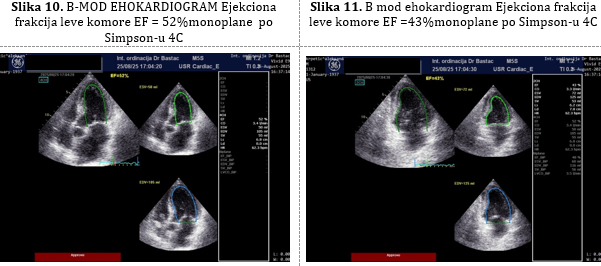

Rutinska kontrola posle 2 meseca 25.08.2025. godine. Pacijent

bez tegoba, ima još 2kg manje, noge ne otiču, nije više

hipotenzivan. Impresivan porast Hemoglobina na 128 g/L zbog terapije

gvožđem ali i zbog korigovanja hemodilucije. Normalizacija bubrežne

funcije GFR=64mL/min/1,73m². Ultrazvučnim pregledom srca (Slike 9,10

i 11) se registruje odličan porast ejekcione frakcije M mod EF 47%,

a po Simpsonu BIPLEJN EF je 46% uz redukciju dilatacije leve komore

(LK EDD=50mm, a ESD=40mm) i iščezavanje plućne hipertenzije (RVSP

=25 mmHg).